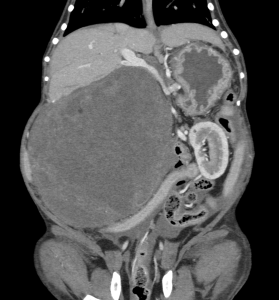

今回治療させていただいたワンちゃんは、ここ1年ほどでお腹が張ってきており、散歩中に立てなくなったとの事で来院されました。原因は、巨大な脾臓腫瘍と、脾臓腫瘍から壊死物質が漏れたことによる腹膜炎でした。重度の貧血を呈していたため、輸血で状態を安定化し、翌日に手術を行いました。脾臓腫瘍は、直径20センチ、重さ2.7kgで、病理組織学的検査は「脂肪肉腫」でした。幸いなことに、手術前のCT検査で転移所見はありませんでした。